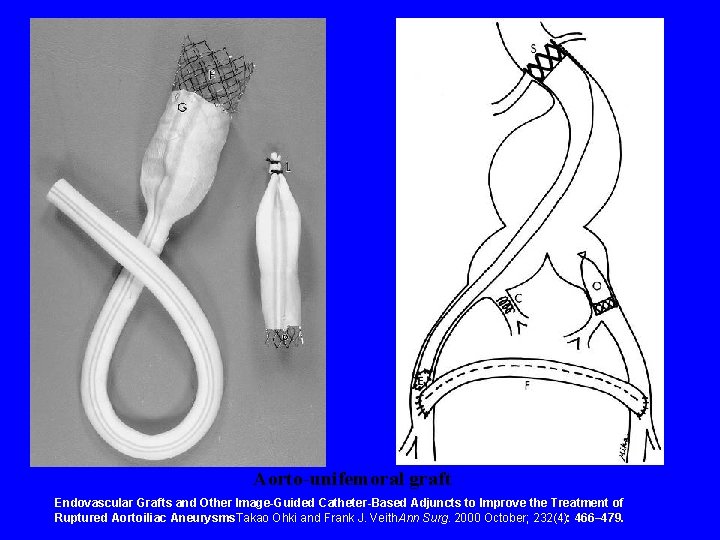

Surgery Endovascular Repair • Stratagies for Repair: – Aorto-unifemoral graft ipisalateral internal iliac exclusion and a femorofemoral crossover graft (Montefiore group) – Modular aortouniiliac and aortobiiliac • Now rupture kits for repair

Aorto-unifemoral graft Endovascular Grafts and Other Image-Guided Catheter-Based Adjuncts to Improve the Treatment of Ruptured Aortoiliac Aneurysms. Takao Ohki and Frank J. Veith. Ann Surg. 2000 October; 232(4): 466– 479.